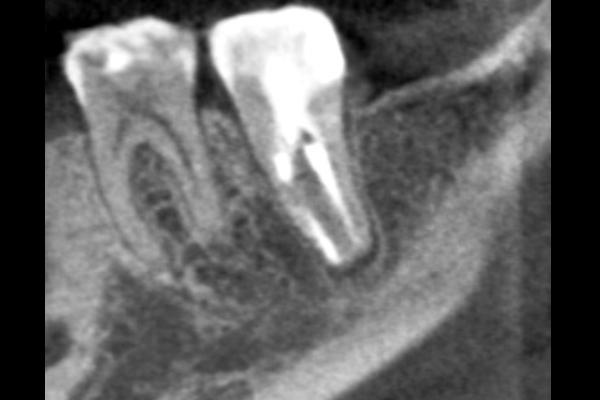

40代男性の大臼歯(奥歯)の症例

- 主訴

- 「時々歯茎が腫れる」とのことでご来院されました。数週間前から症状があり、他の医院では「抜歯の可能性がある」と言われ、不安に感じていらっしゃいました。

- 期間

- 治療期間2ヶ月、治療回数3回、レントゲン写真で治癒を確認できるまでの期間6ヶ月

- 治療内容

- 1.古い被せ物の除去と虫歯の徹底除去

まず、古い銀歯を外し、内部に広がっていた虫歯を丁寧に取り除きました。

2.マイクロスコープ下での根管治療

唾液などによる細菌の侵入を防ぐ「ラバーダム」を装着し、マイクロスコープ(歯科用顕微鏡)で根管内を数十倍に拡大しながら治療を進めました。複雑な形状の根管の内部まで、汚染された組織を徹底的に洗浄・消毒します。

3.根管充填(こんかんじゅうてん)

根管内が完全にクリーンになったことを確認し、再感染を防ぐために専用の薬剤で隙間なく密閉しました。

4.土台と被せ物の作製

歯の強度を補うための土台を立て、最終的なセラミックの被せ物を作製し、装着しました。